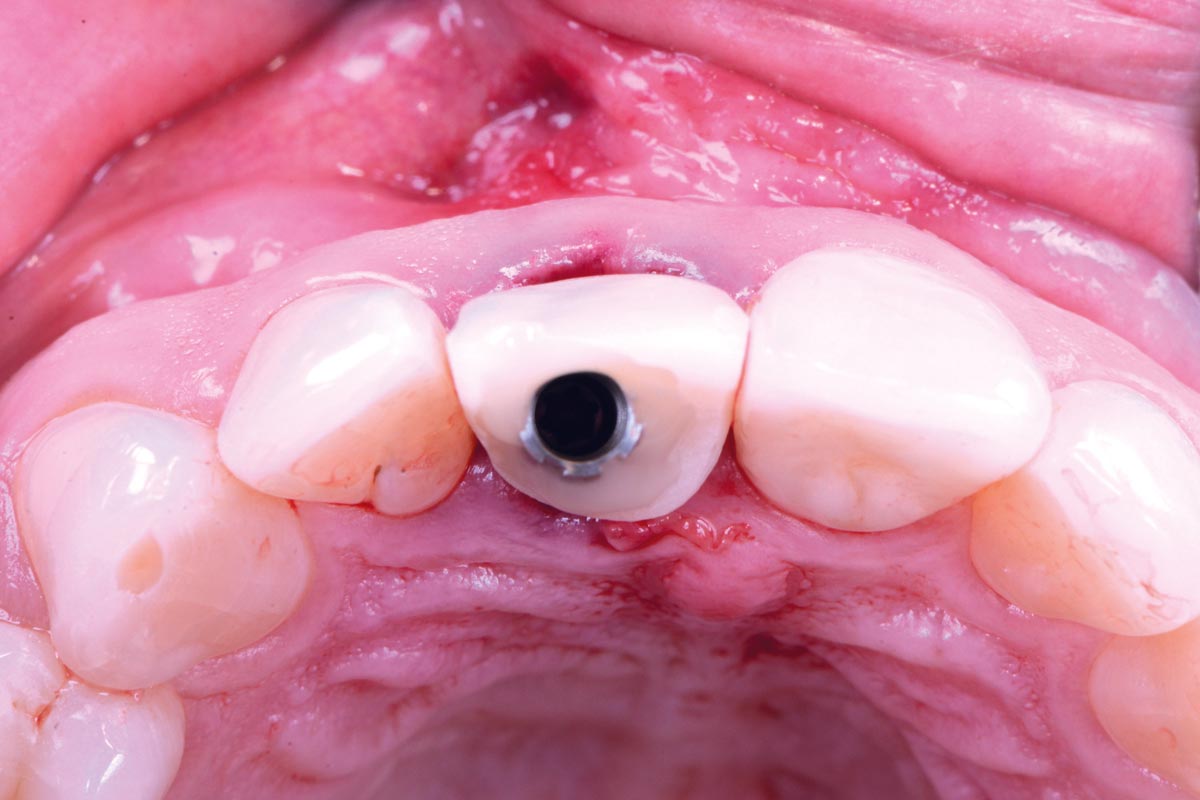

cerabone® and mucoderm® for immediate implantation in the aesthetic area - Dr. D. Robles

Initial clinical situation - Central incisors with dental destruction and periapical pathology